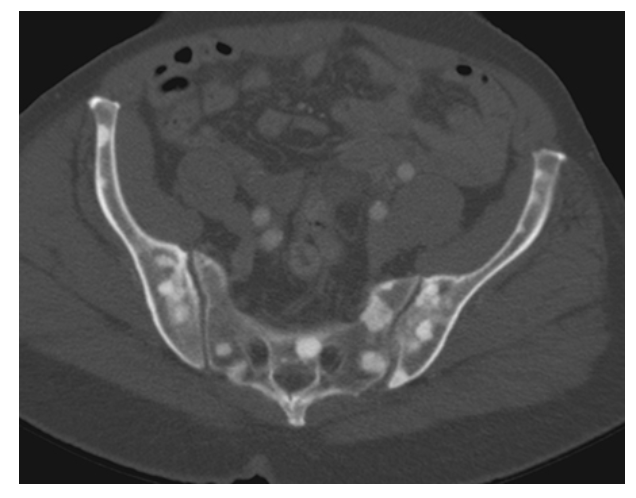

Breast Cancer. CECT with bone windows shows multiple osteoblastic breast cancer metastases within the sacrum and iliac wings.